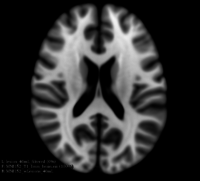

This module offers a simulation toolkit for baseline Multiple Sclerosis (MS) brain lesion volumes (given a lesion load) and longitudinal image simulations, respectively. In summary, a statistical lesion database is generated based on a set of manual lesion mark-ups, being non-linearly registered to MNI152 space (isotropic 1mm of voxel resolution). Using a small set of parameters (lesion load, lesion homogeneity, lesion intensity independence and lesion variability), it is possible to generate a broad range of MS lesions patterns in multimodal MRI imaging techniques (at moment, T1, T2, T2-FLAIR, PD, DTI-FA and DTI-ADC images are provided).